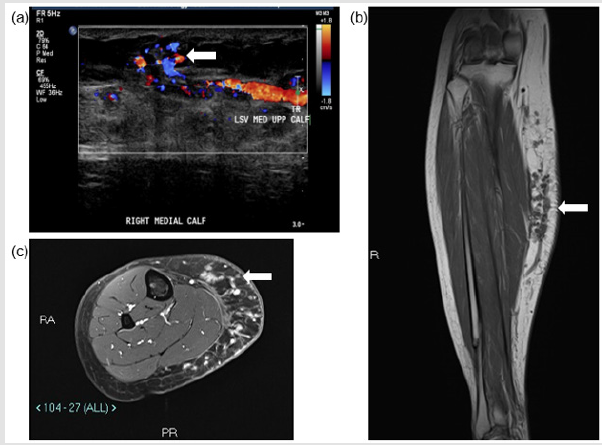

A 32-year-old lady (ASA 1; BMI 25.1) presented to the specialist vascular outpatient clinic with worsening swelling and pain of her right calf for the past 2 years. Onset was originally noted 10 years ago following a road traffic accident, which caused a right tibia-fibula fracture and significant bruising to her right calf. She had undergone a radiofrequency ablation of her symptomatic right above knee GSV varicosities (CEAP 3 disease) 3 years prior at an external institution; however, the pain and swelling persisted almost immediately post-operatively. She also described the feeling of heaviness especially towards the end of the day, which was affecting her quality of life and her work as a hairdresser. She had noticed that the varicosities she previously had were reappearing and that the skin over her shin and ankle had darkened. She had a CEAP score of C4b Es As Pr and a revised Venous Clinical Severity Score (rVCSS) of 14. A venous duplex ultrasound scan revealed an incompetent deep venous system, saphenous-femoral junction (SFJ), and GSV along its entire length, which had recanalized proximally and was patent to the foot (Figure 1a).

The maximum diameter of the GSV was 8 mm just distal to the SFJ and the rest of the GSV ranged from 3-5mm in maximum diameter to the mid-calf region. Tortuous channels of vessels were noted at the medial aspect of the calf with areas of thrombosis. The patent tubular channels demonstrated venous flow. No significant arterial supply was noted. Appearances were in keeping with a low flow vascular anomaly, with predominantly a venous component. A dominant dilated vein appeared to communicate with the GSV at the level of the knee joint and within the distal calf (Figure 1b). MRI of the right calf demonstrated numerous small rounded high signal T1- and T2-weighted lesions within the subcutaneous fat planes of the medial aspect of the right calf. The lesions enhanced post-contrast without any evidence of solid mass or rim enhancing collection. There was no evidence of involvement of the musculature (Figure 1c). A diagnosis of a slow flow VM was made by the hospital’s AVM multi-disciplinary team consisting of a vascular surgeon, interventional radiologist and muscular-skeletal radiologists. It was decided to treat the lesions endovascularly using a combination of VCS and sclerosant (2.0% liquid sodium tetradecyl sulphate (STS), FibroveinTM, STD Pharmaceutical Products Ltd, Hereford, UK).

Figure 1: Pre-procedural assessment of the right medial calf vascular malformation. (a) US shows superficial venous structures communicating with GSV tributary. (b) T1w coronal image of the right calf demonstrating vascular structures within the subcutaneous fat of the right calf communicating with a superficial tributary of GSV. (c) Axial STIR images demonstrating the subcutaneous venous malformation.